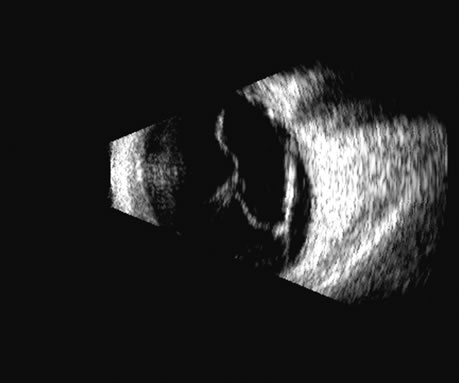

Fig. 2. Ciliary body retroiridal cyst can be demonstrated in this occult area as clear, usually rounded, single or multiple cystic spaces. They are nearly always clear acoustically and may at times contact the lens and occasionally cause cataract formation.

Fig. 3. Solid tumor of the ciliary body, often appearing relatively round, but occasionally irregularly shaped to match the area of the ciliary body itself. It can be presented in 3D for measurement of growth, but usually these highly lethal tumors are treated soon after presentation.